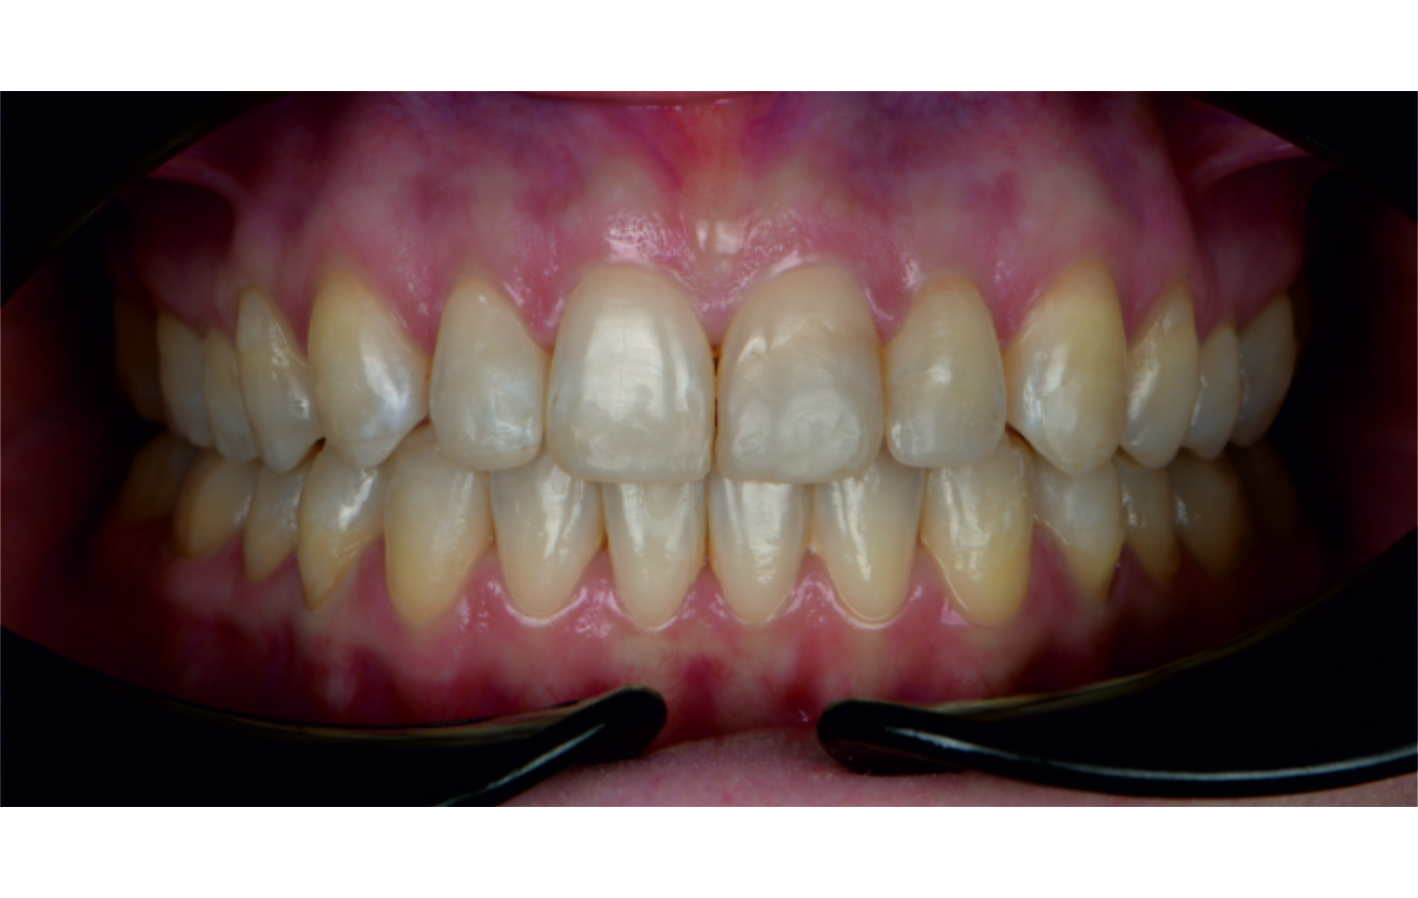

Angel Aligner PRO: Correction of a class II div 1 malocclusion

By Dr. Dalia Latkauskiene

This case, led by Dr. Dalia Latkauskiene, presents the treatment of a 25-year-old female patient with a Class II division 1 malocclusion. Using the Angel Aligner PRO system with dual-modality mechanics, the treatment achieved derotation of molars, midline correction, open-bite closure, and Class I settling. In just 12 months and 40 aligners, the approach delivered precise control, enhanced function, and a significantly improved smile.